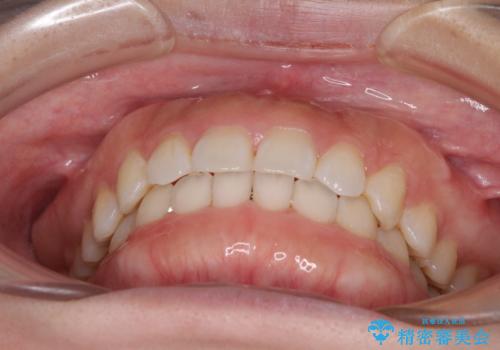

1日22時間の装着時間をしっかり守ってくださったので、1年程度で治療を終えることができました。

1セットのマウスピースで概ね治療を終えたのですが、前歯僅かな叢生が残ったため、2セット目のマウスピースで仕上げました。

気にしていた口元の印象が改善され、患者様には大変満足していただきました。